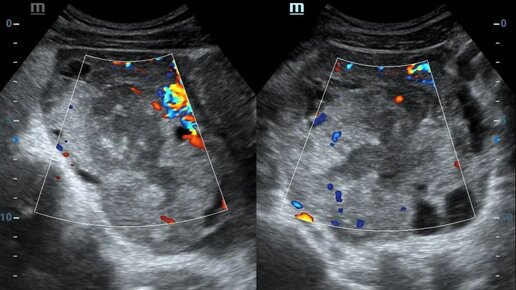

Показания Ультразвуковое обследование органов малого таза у женщин – информативный и надежный способ подтверждения диагноза, предварительно поставленного врачом-гинекологом. Применяется 2 разных вида датчиков: абдоминальный и трансвагинальный. После обследования через брюшную стенку врач исследует шейку матки и стенки влагалища с помощью вагинального датчика.  Таким способом проверяют состояние лимфатических узлов, увеличение которых часто является признаком злокачественного процесса. При лечении...

Значимое место среди современных методов диагностики занимает УЗИ малого таза. Пациенты Real Clinic могут оценить состояние своей мочеполовой системы при помощи этого безопасного и безболезненного способа, который обладает высокой степенью информативности и точности. А по результатам исследования врач поставит диагноз и подберет эффективную схему лечения. Узи малого таза: показания и результаты Как работает аппарат УЗИ Метод основан на особенностях ультразвуковых волн. Все органы человеческого тела...